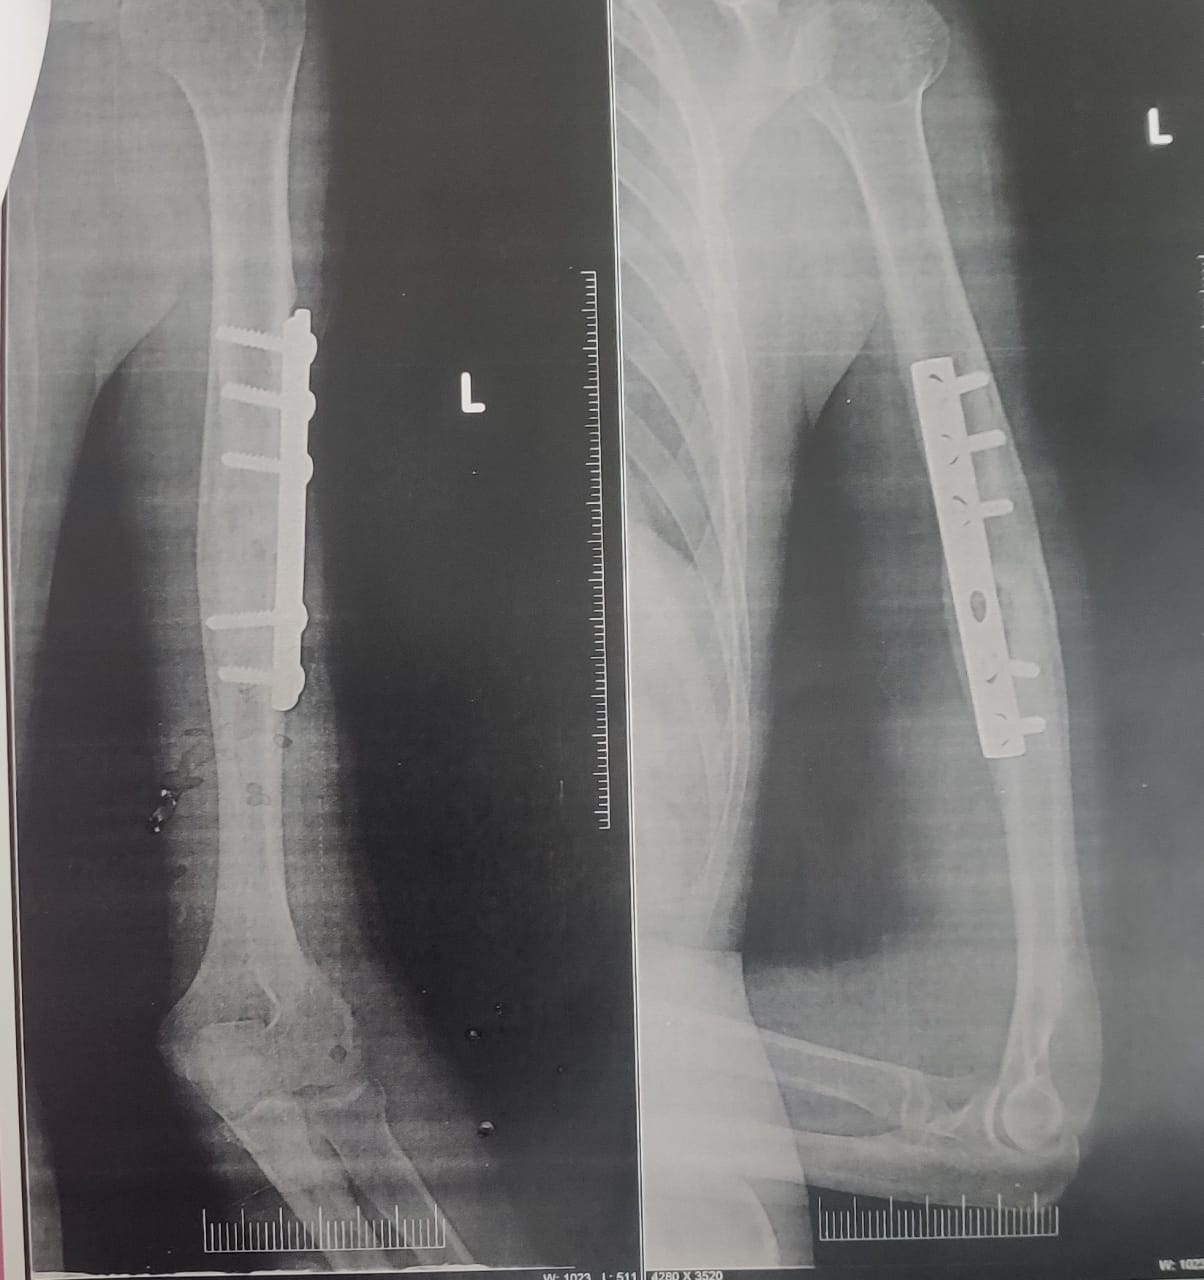

Patient has a history of fracture to the left arm following an accident, it is fixed with a DCP plate .